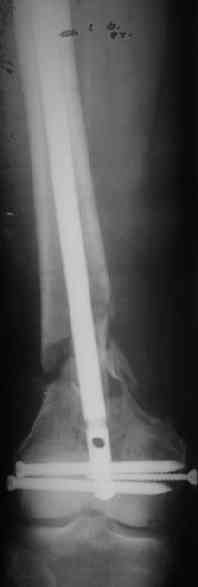

Удалили ластину без проблем. Выявилась значительная подвижность. В этих условиях сразу пропала мотивация к постепенной коррекции аппаратом. Попробовал восстановить длину, введя между отломками spreader. Отчасти удалось. Тогда защили рану, наложили спицевой дистрактор (2 спицы в дистальный отдел и 1 вверху). после этого был убран и спонгиозный винт. И сделали антгерадное штифтование, как говорится, "по принятой в

клинике методике".

Длину восстановили, возможно, даже с изьбытком, ну да динамизируем пораньше. Введенные в овальное отверстие дистальые винты имеют угловую стабильность. Снимки приложены. Заранее спасибо за критику и комментарии.